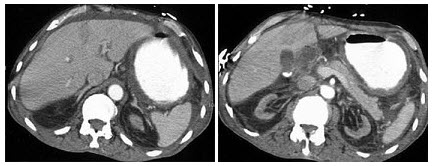

E.明显强化

17、单项选择题

男,67岁,排便习惯改变,血便3月入院,CT检查如图所示,下列说法错误的是()

A.直肠肠腔局限性增厚

B.其表面欠光整,边界欠清晰

C.可做直肠指检及活检以确定病变性质

D.此为直肠息肉

E.此为直肠癌